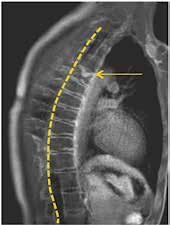

Die erst gegen Ende der Pubertät auftretende Hyperkyphose des Morbus Scheuermann (Abb. 3) entzieht sich durch den Zeitpunkt ihres Auftretens und damit ihrer späten Diagnostik einer effektiven Orthesenbehandlung 10 11 12. Das Potenzial der Orthesenversorgung zur Verhinderung einer Kyphoseprogredienz ist jedoch in Einzelfällen zu nutzen. Besonders Kyphosen im kaudalen Brustwirbelsäulenbereich bieten dabei günstige Hebelverhältnisse.